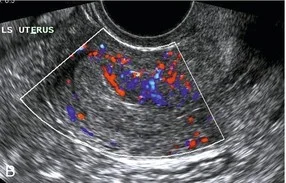

- U/S and Doppler study.